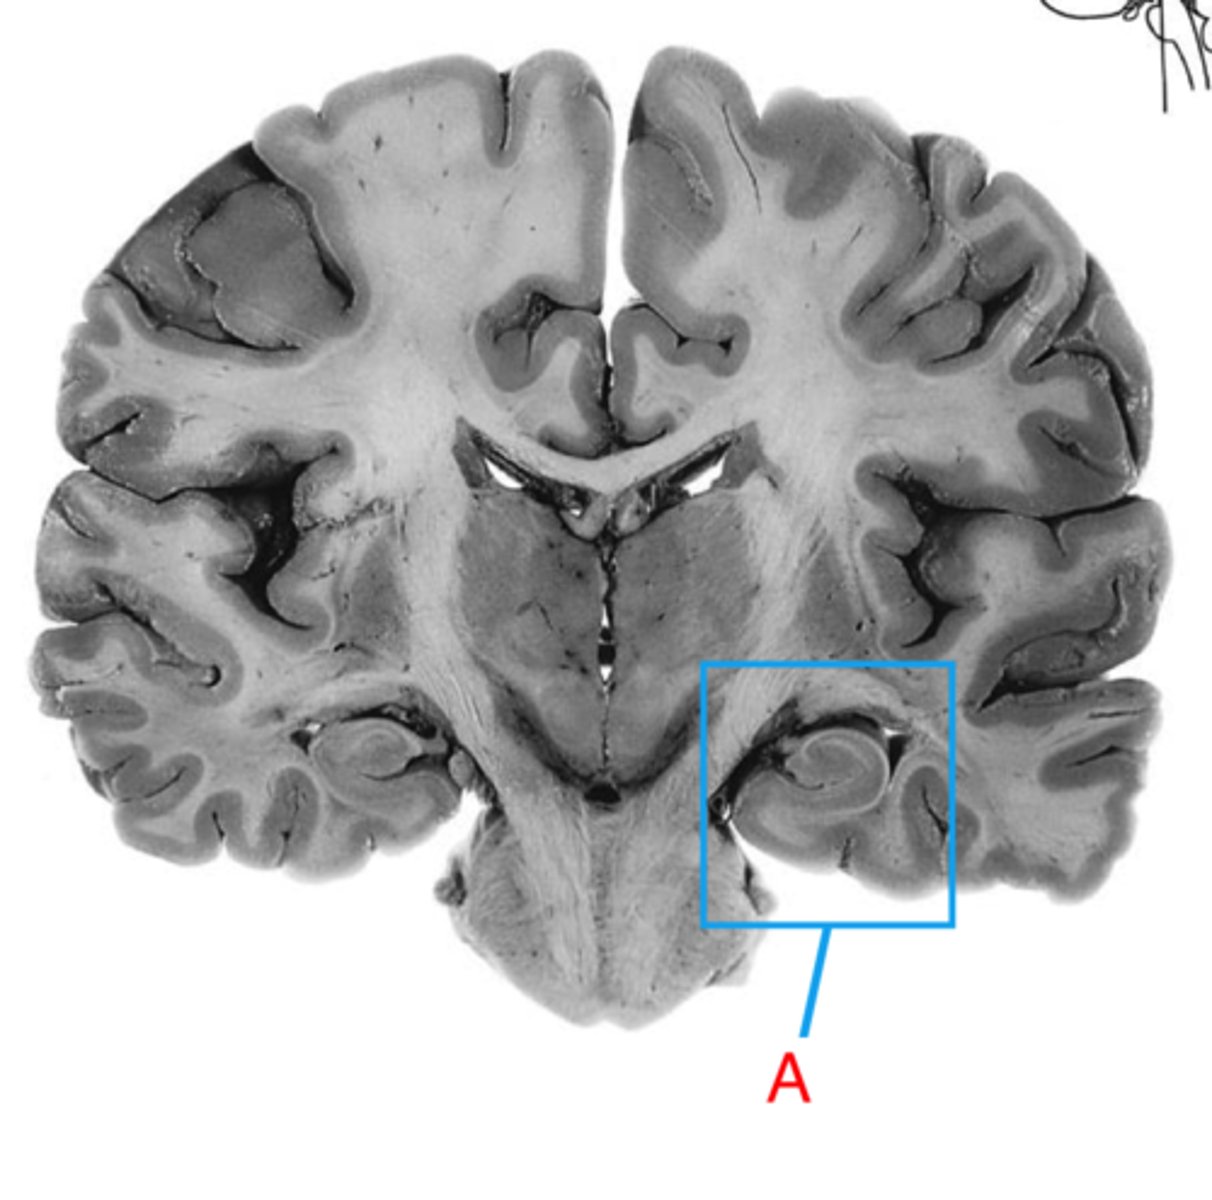

hippocampus

the region of the brain more caudal than the amygdala, snail appearance medial in the temporal lobe. Appears with the thalamus+third ventricle. plays a role in memory.

amygdala

rounded shape located medially in the temporal lobe. Appears with the hypothalamus, more rostral than the hippocampus. Plays a role in emotion.

inferior horn of lateral ventricle

located in the temporal lobe of the brain. It is the largest of the three horns and extends from the atrium, curving anteriorly and inferiorly to go under the thalamus and into the temporal lobe